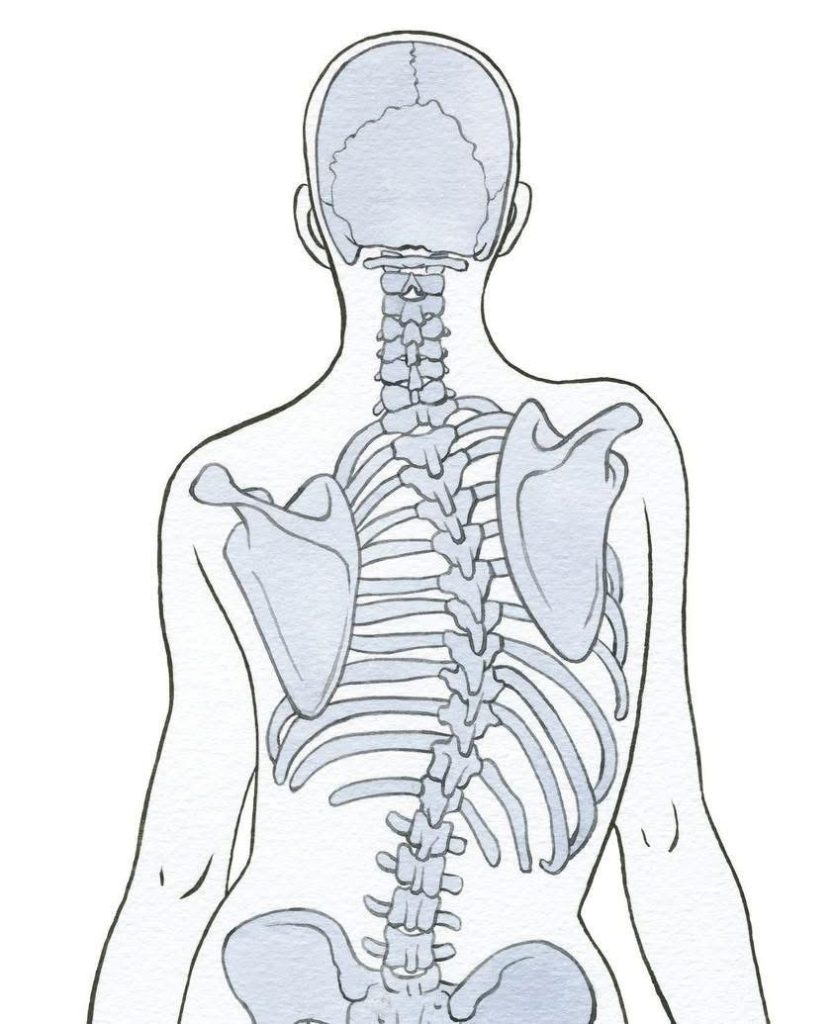

انحناء العمود الفقري (Spinal Curvature)

هو تغيّر غير طبيعي في شكل أو محور العمود الفقري، وقد يكون بسيط أو شديد حسب الدرجة والسبب

الجنف (Scoliosis)

• انحناء جانبي على شكل C أو S

• قد يكون وظيفي (بسبب وضعية خاطئة) أو تركيبيويوجد منه شكلين

1. جنف على شكل C

• انحناء واحد

• أكثر شيوعًا في الحالات البسيطة

2. جنف على شكل S

• انحناءين متعاكسين

• أكثر تعقيدًا ويحتاج متابعة دقيقةيمكن اكتشافه عن طريق الإكلينيكية

عدم تساوى الكتفين

ميل ف الحوض

اختلاف ف المسافه بين الذراع والجذع

ويوثر ايضا ع الرجلين

بروز احد لوحى الكتف بشكل ملحوظ